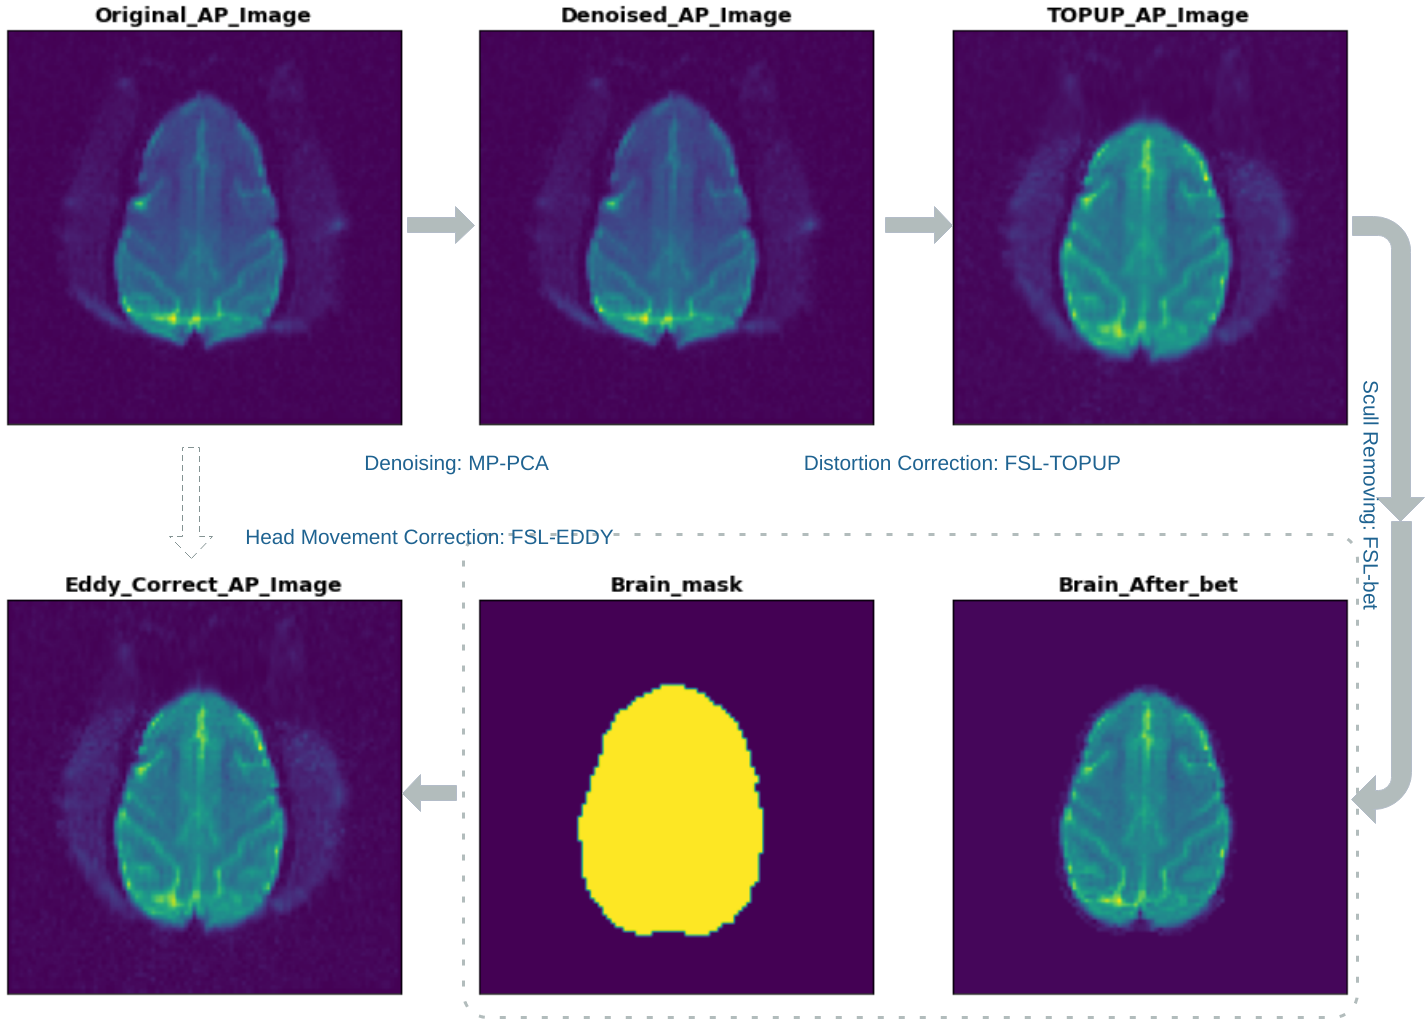

Preprocessing results

This project started with medical imaging data format, then preprocessed the diffusion weighted images, which includes MP-PCA denoising, FSL TOPUP distortion correction and head movement correction. After this, DTI images were reconstructed from these preprocessed images successfully. Additionally, a dataset for left and right hemispheres classification was generated from these preprocessed images. By using the KNN method, classification accuracy of 92% was reached. As a starter, I will continue this project in the future. Soon, self-made models, instead of DTI model, will be used to reconstruct diffusion images. After that, I would like to use machine learning methods to classify potential changes of brain microstructures.